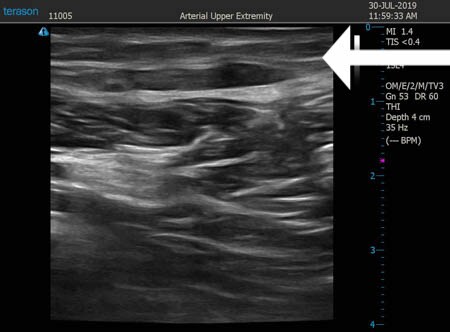

いつものように3Dタッチビュー(超音波)で

皮下脂肪層を評価してみましょう。

右太もも後面。

上の画像の部分の皮下脂肪層をつまんでみましょう。

同様に左太もも後面。 ↓ ↓ ↓

比較的柔らかくて吸引しやすい皮下脂肪でした。